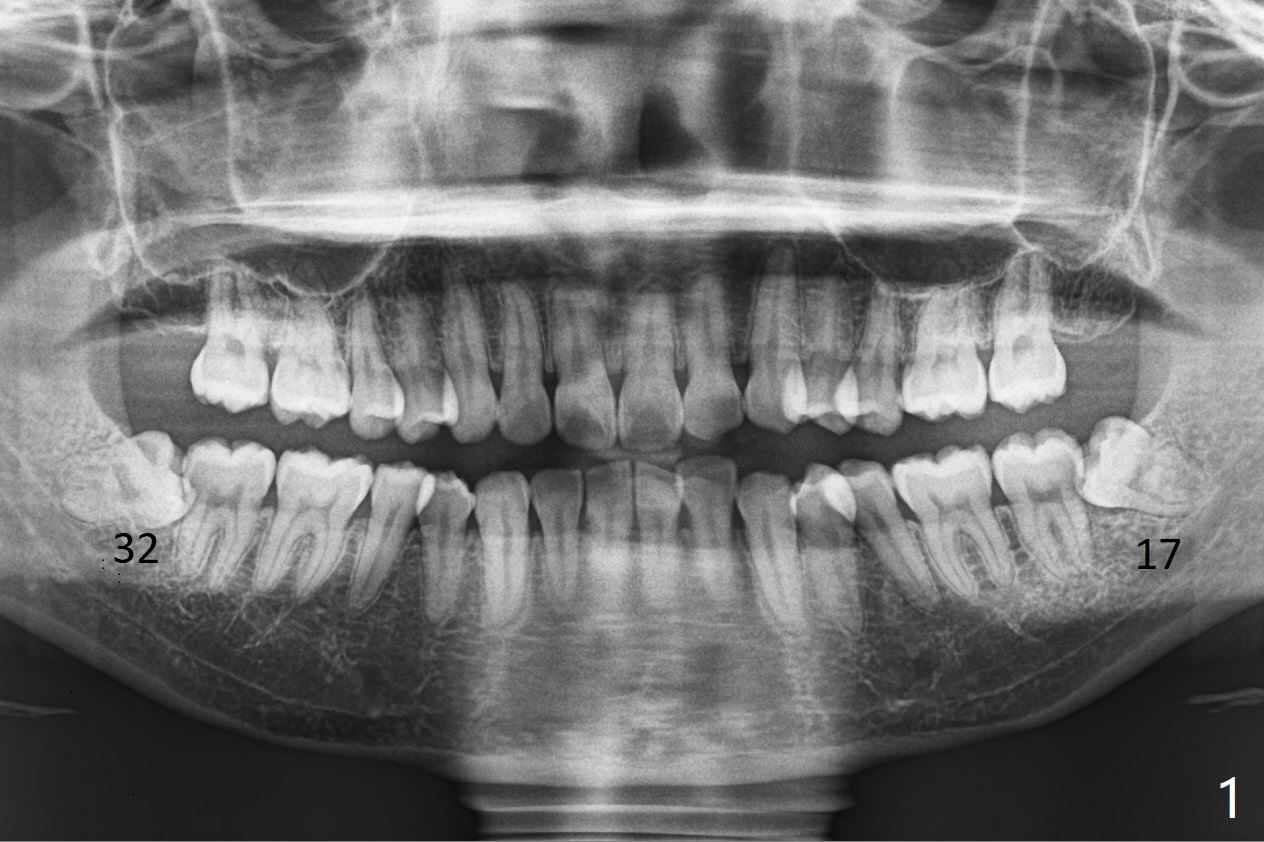

A 28-year-old woman returns for #17 and 32 extraction. To obtain full potential of bone regeneration after extraction, 3 D Bond (Graft Binder Cement, .5 cc, Fig.2 C) will be placed in the root portion of the socket of #32 , while allograft (G) and Collagen Plug (P) in the coronal one. For comparison, Osteogen Plug (Fig.3 O) will be inserted in the root portion of the socket of #17, while the other two materials same as those at #32. Take postop panoramic bitewing if both teeth are extracted. Otherwise take PA. Place the latter in the center of the extraction socket.

In fact the tooth #32 is extracted first; the defect involves the distobuccal aspect of the tooth #31 (Fig.4 *). An intraop PA is taken after extraction to confirm whether a broken surgical fissure bur tip retains or not; the distal lamina dura of #31 is low (Fig.5 *). It is expected to increase after cocktail bone graft (Fig.5' arrow). As planned, the bone cement (Fig.6 C) and allograft (G) are placed in the distal and mesial portions of the socket; between them is Osteogen Plug (O). Another piece of Osteogen Plug (as collagen membrane for bone graft) is placed on the top of the socket before suturing with 4-0 Plain Gut (Fig.7,7' O). Also note the bone graft being placed distobuccal (CT study) to #31 (Fig.7' red dashed line) to reduce possibility of future periodontitis. The patient returns 15 days postop with chief complaint of mild pain since extraction, although the wound looks normal. The transverse cortex connecting to the lamina dura (Fig.5 *) is obliterated when allograft is placed (Fig.7 G). The part of the graft remains in place 1 month postop (Fig.9) in spite of wound dehiscence (Fig.8). The bone graft loss is indicated by the fact of the reappearance of the transverse cortex (Fig.9). In the same appointment, the tooth #17 (Fig.10) is being extracted (Fig.11), leaving a defect mesiobuccal (Fig.12 *) to distal (curette). Part of Osteogen plug (Fig.13 O) is stretched to cover the mesially placed allograft (Fig.14 G). One quarter of Collagen plug is placed over the Osteogen plug (Fig.13 O) before 4-0 PGA suturing. There is bone regeneration 1 year postop (Fig.15,16).